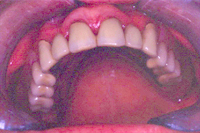

In Abb. 4 sieht man die Oberkieferteilprothese (Innenansicht) mit den vier Haltemechanismen (Druckknöpfen). Im Mund eingesetzt, bietet dieser Zahnersatz sehr guten und sicheren Halt (Abb. 5). Ausser regelmässigen, halbjährlichen Kontrollsitzungen bei der Dentalhygienikerin war an diesem Zahnersatz bis heute nie ein weiterer Eingriff nötig. Die Patientin ist sehr zufrieden (Abb. 6).